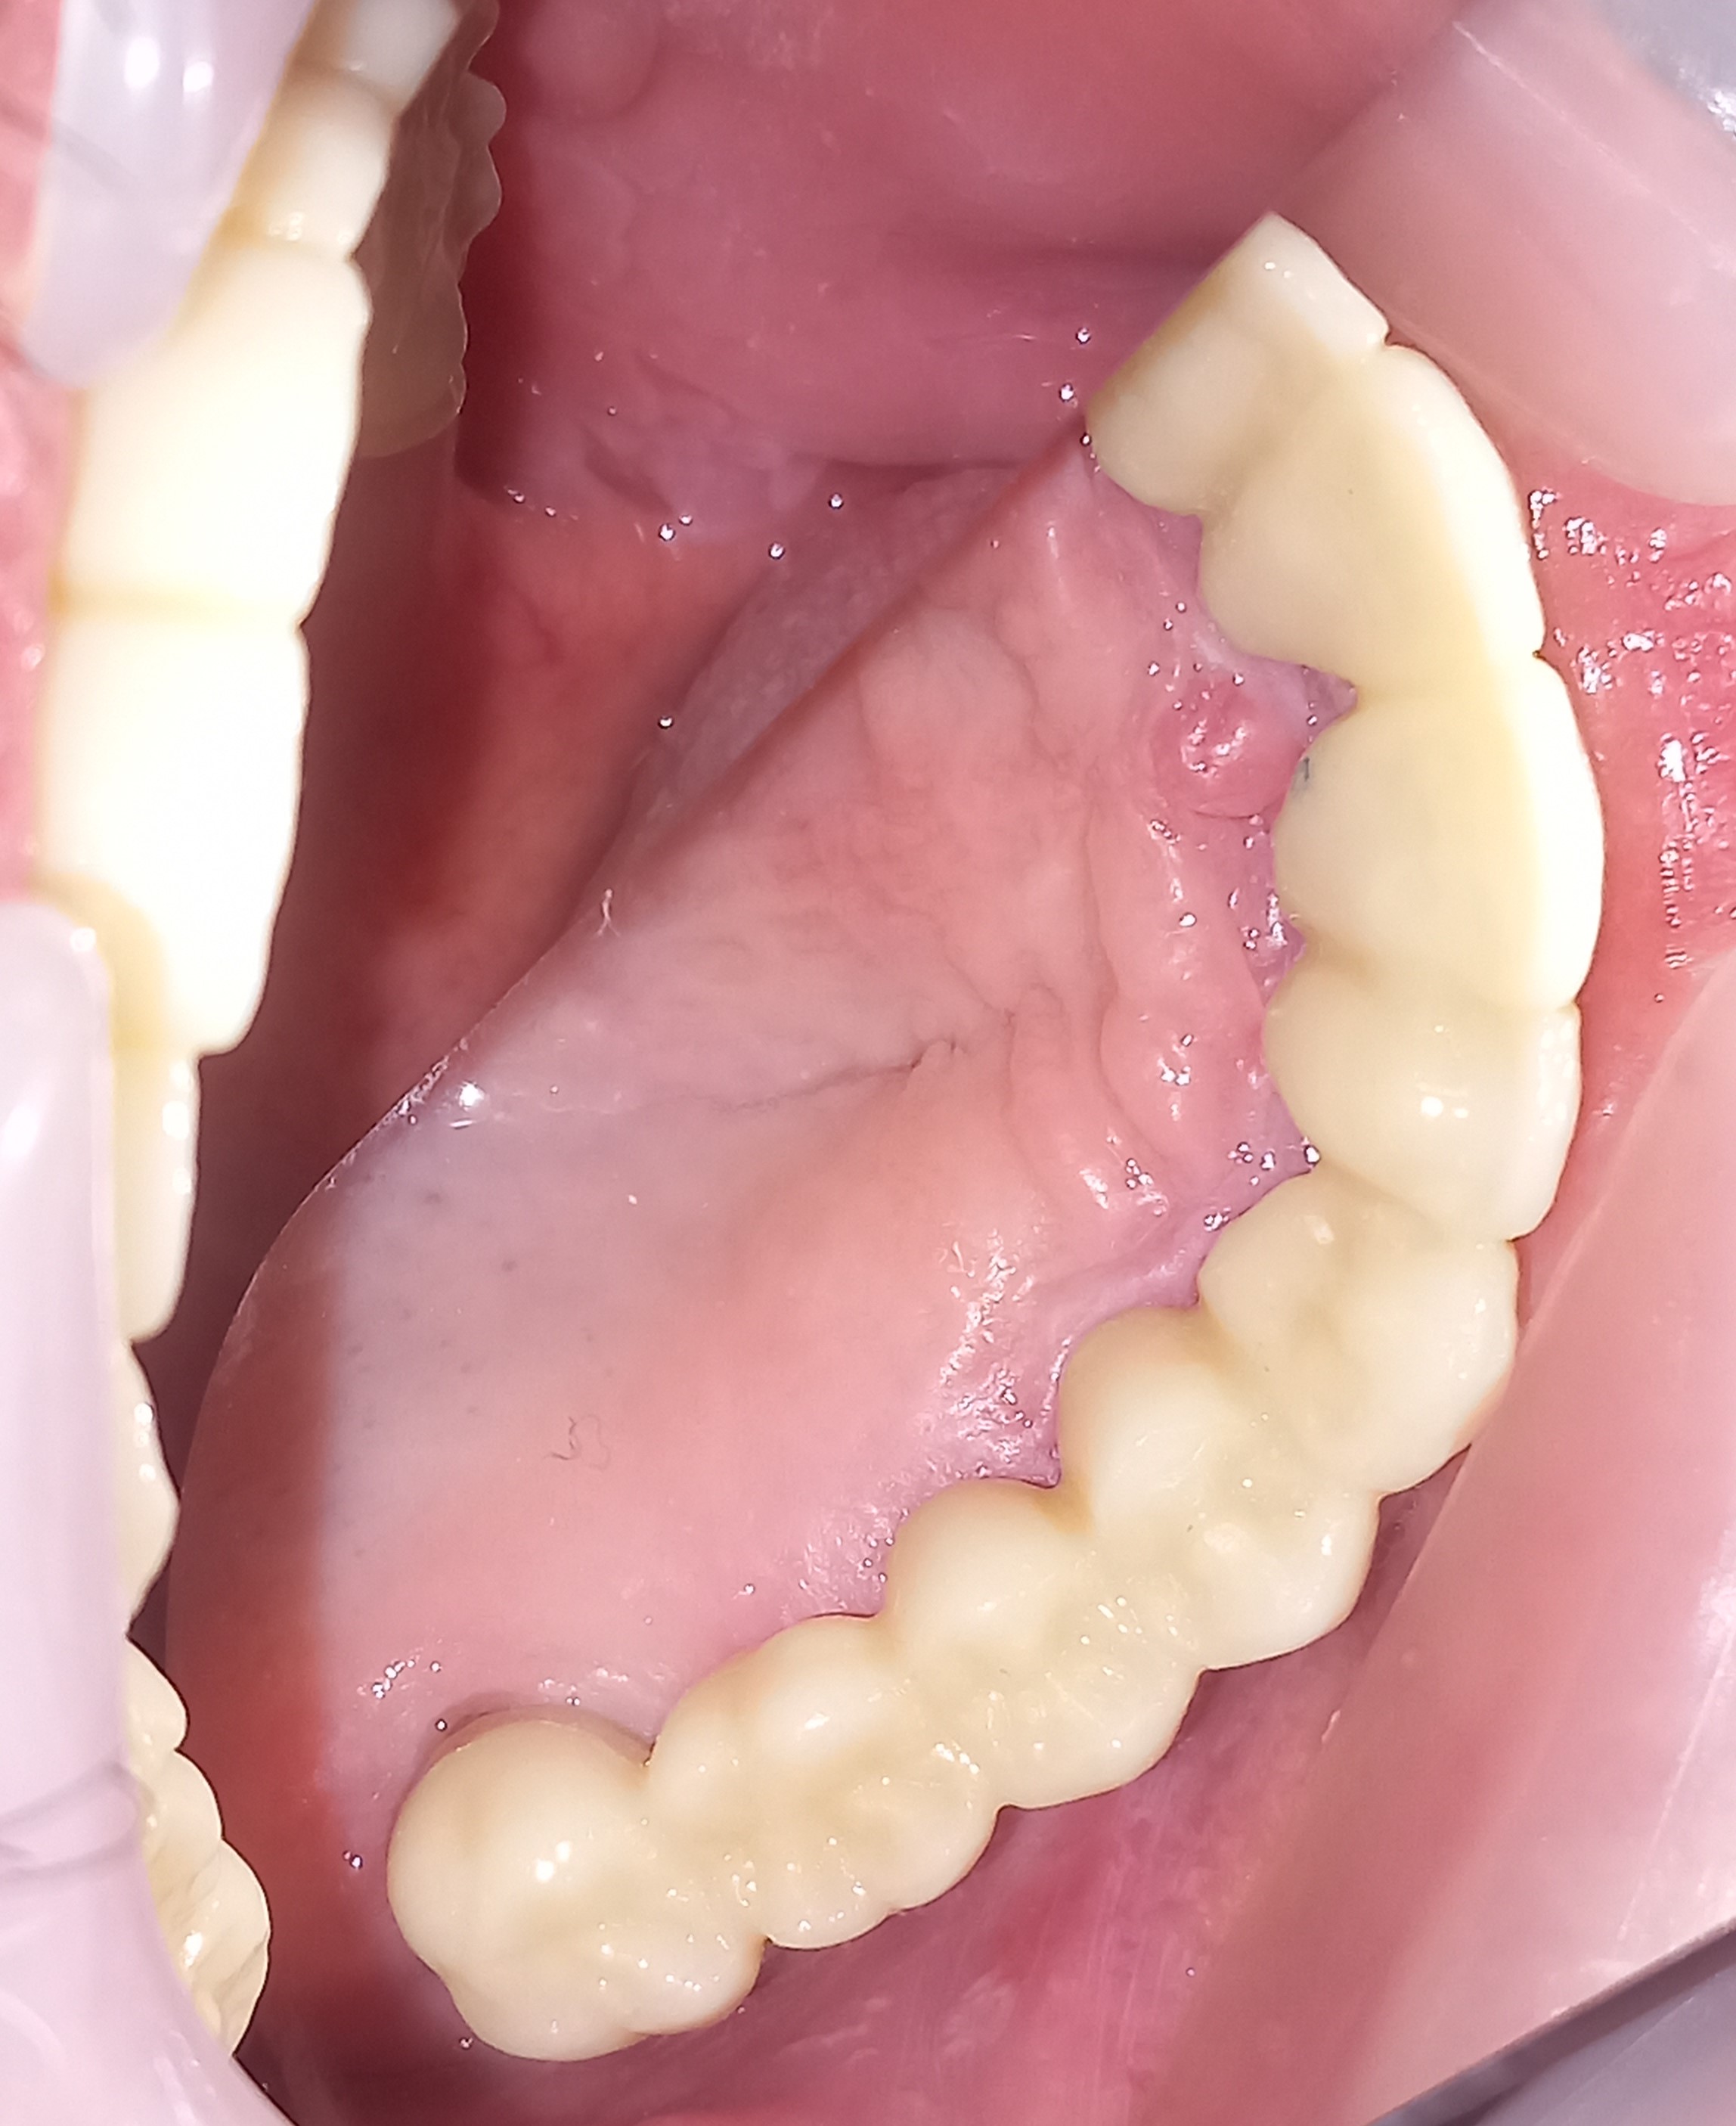

Τελική εικόνα του ολοκεραμικού πέταλου ζιρκονίου στην κάτω γνάθο

Τελική εικόνα του ολοκεραμικού πέταλου ζιρκονίου στην κάτω γνάθο

Ο ασθενής πήρε την απόφαση μετά από πολλά χρόνια να αποκαταστήσει τα δόντια τόσο της άνω γνάθου όσο και τα δόντια της κάτω γνάθου. Χρειάστηκαν αρκετές συνεδρίες ώστε να ολοκληρωθούν οι απαραίτητες απονευρώσεις και ανασυστάσεις δοντιών. Στη συνέχεια και εφόσον ήταν έτοιμη η προσθετική δουλειά από τον οδοντοτεχνίτη κολλήθηκαν τα ολοκεραμικά πέταλλα στο στόμα του ασθενή.

Τελική κλινική εικόνα της μασητικής επιφάνειας των κάτω δοντιών